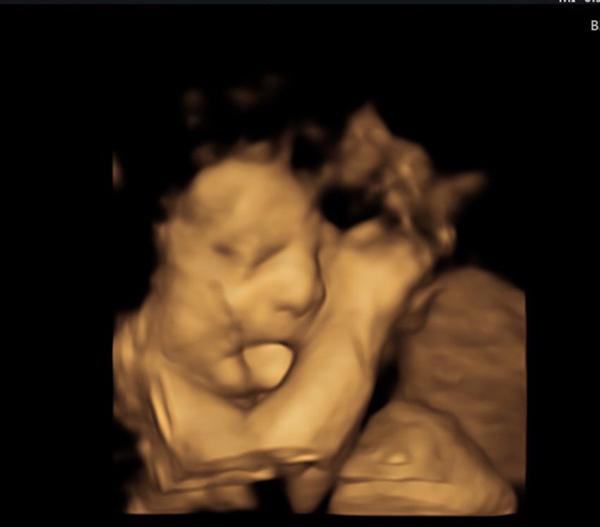

Khi siêu âm thai 27 tuần, bà mẹ này và cả bác sĩ đều thấy thú vị khi em bé "lè lưỡi" ra nhưng không ngờ đây là một dấu hiệu nguy hiểm.

Vậy nhưng cậu bé đã vượt qua mọi khó khăn để tiếp tục phát triển. Thậm chí khi đi siêu âm 27 tuổi, vợ chồng Farah và bác sĩ còn rất thích thú khi nhìn rõ em bé đang lè lưỡi như đang tỏ ra đáng yêu.

Vợ chồng Farah và bác sĩ đều khen em bé đáng yêu khi thè lưỡi lúc siêu âm.

Khi nhìn mặt con, hai vợ chồng cô đều bất ngờ vì chiếc lưỡi của bé to gấp đôi bình thường, vừa dày vừa dài khiến Baker không thể ngậm miệng lại được.

Sau đó, bác sĩ cho biết Baker mắc hội chứng Beckwith Wiedemann (BWS), một rối loạn phát triển quá mức hiếm gặp ảnh hưởng đến một trong 14.000 ca sinh trên toàn thế giới. Chiều lưỡi "khổng lồ" khiến cậu bé gặp khó khăn khi bú mẹ, ăn và nói.